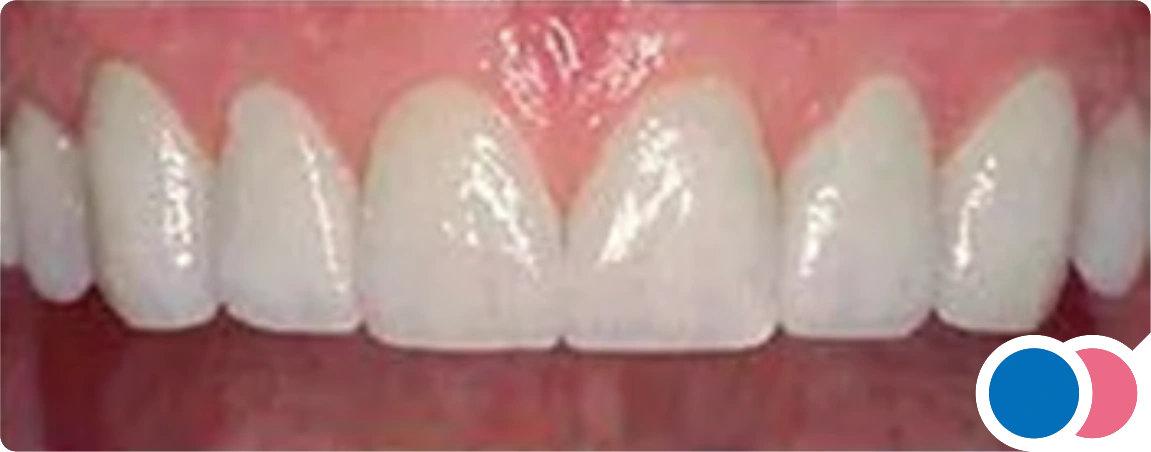

Photograph Requirements

Photograph Requirements